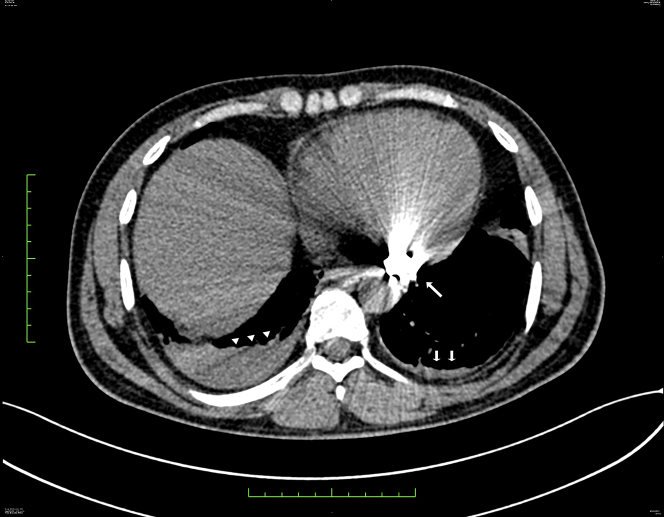

Figure 4.

Nongated Computed Tomography

Image of the thorax showing a foreign body (long arrow) with beam-hardening artifacts obscuring exact localization. There is mild bilateral pleural effusion, right (arrowheads) more than left (short arrows). Minimal pericardial effusion is also noted.

Imaging plays an important role in managing such patients by defining the extent of the injury and chamber involvement. CECT of thorax provides high-resolution imaging to assess the extent of the damage. However, metallic foreign bodies result in beam-hardening artifacts, which may obscure anatomic details. In the present case, CECT was inconclusive and could not exclude an intracardiac location of the bullet. Echocardiography resolved this dilemma and confirmed the location to be intrapericardial (4).